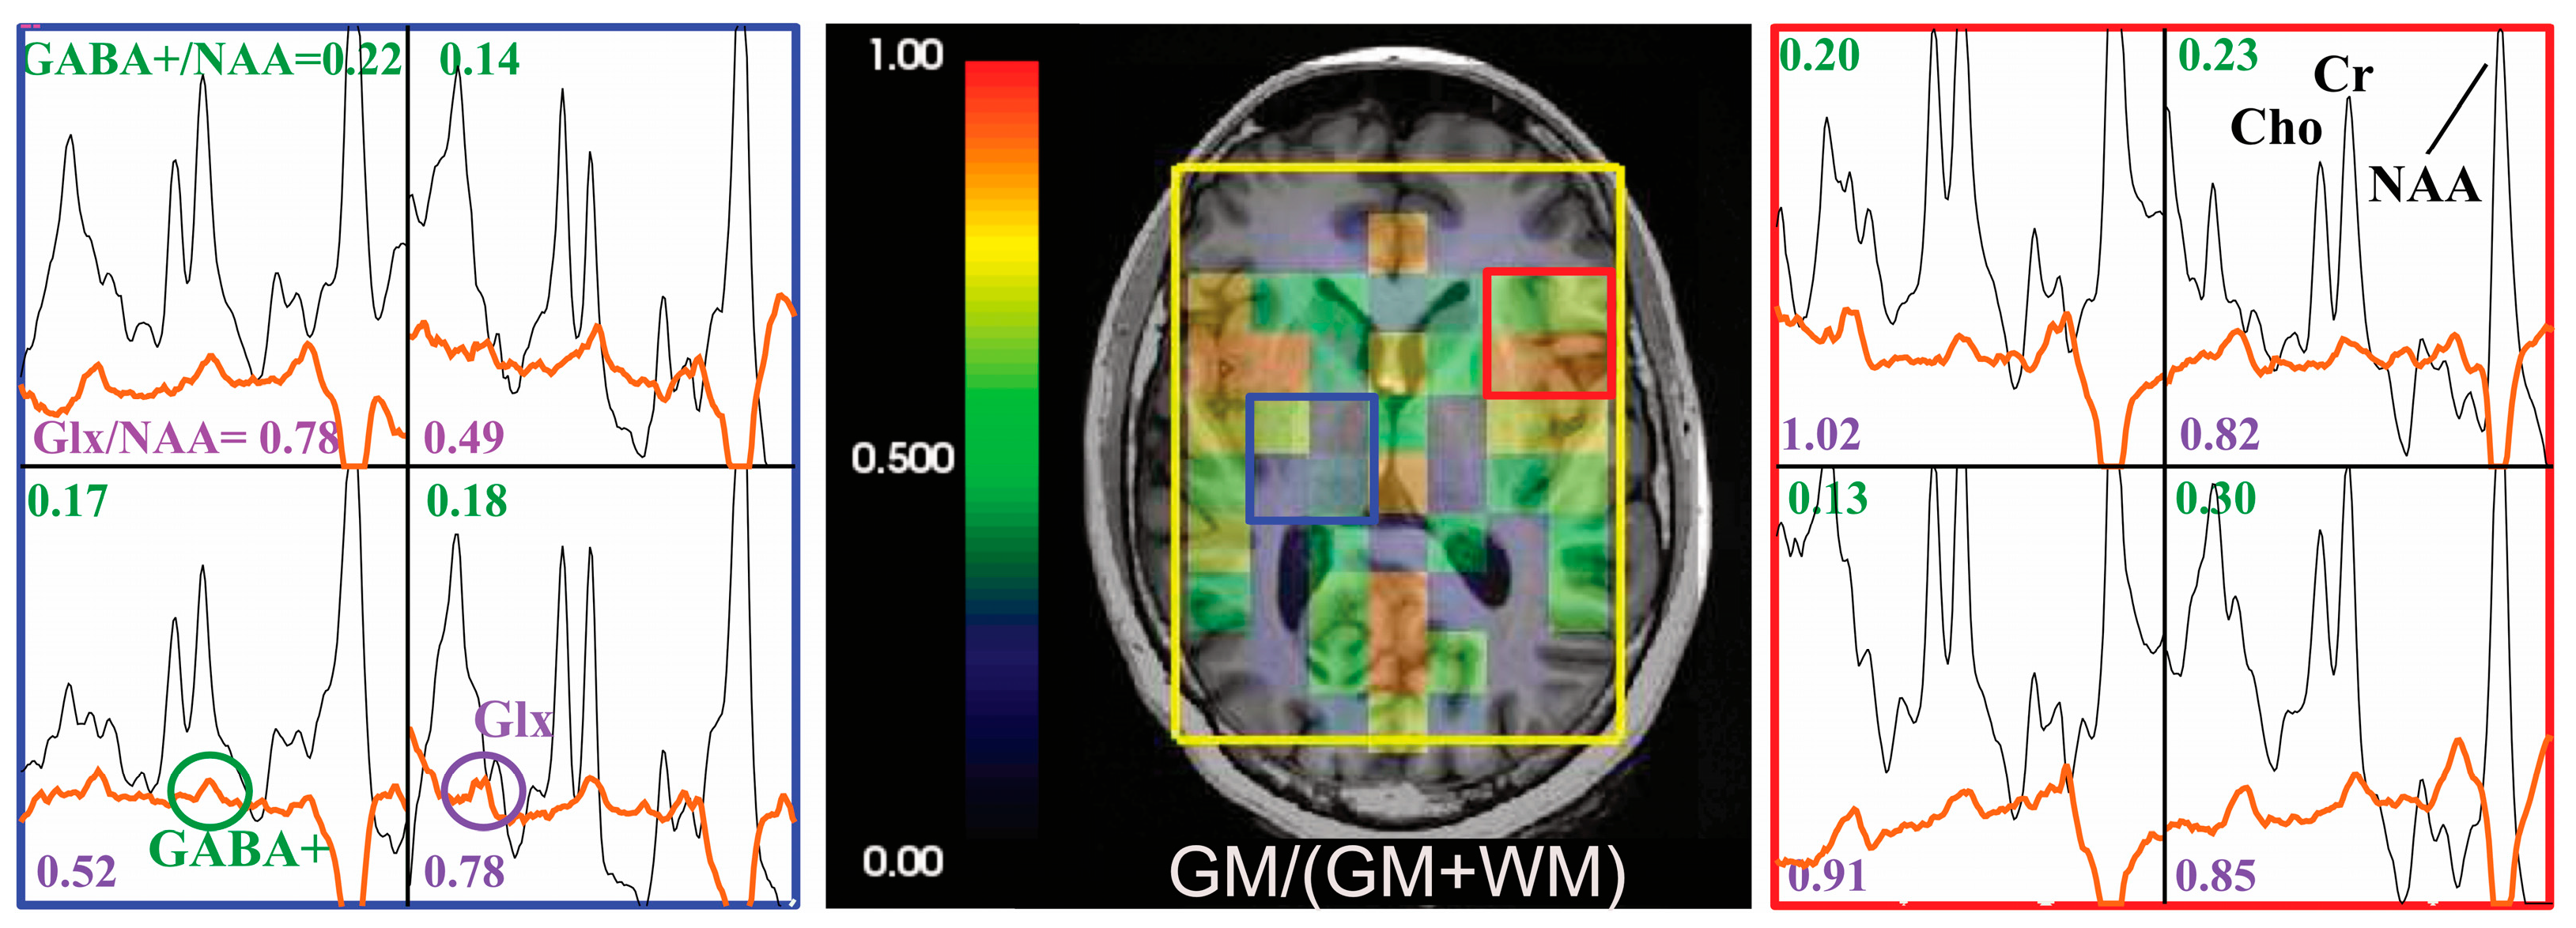

| Location | GABA+/NAA | GABA+/Cr | GABA+ CRLB | NAA CRLB | Cr CRLB | |

|---|---|---|---|---|---|---|

| Top slice | GM | 0.16 ± 0.02 | 0.21 ± 0.02 | 16 ± 2 | 2 ± 0.3 | 3 ± 0.4 |

| WM | 0.14 ± 0.02 | 0.22 ± 0.03 | 16 ± 2 | 2 ± 0.2 | 3 ± 0.2 | |

| Bottom slice | GM | 0.18 ± 0.02 | 0.21 ± 0.04 | 13 ± 5 | 2 ± 0.2 | 3 ± 0.4 |

| WM | 0.16 ± 0.02 | 0.23 ± 0.04 | 15 ± 2 | 2 ± 0.3 | 3 ± 0.4 | |